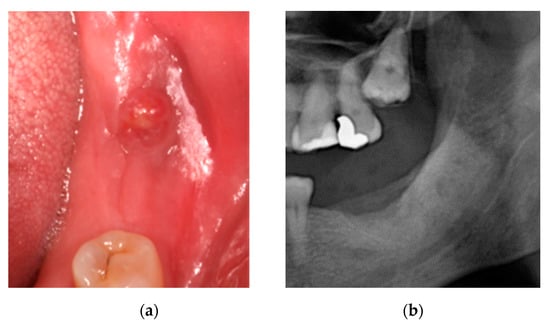

2.1. Case 1: Conservative Treatment

2.2. Case 2: Conservative Treatment Plus Surgery

2.3. Case 3: Conservative Treatment + SURGERY + PRF-L